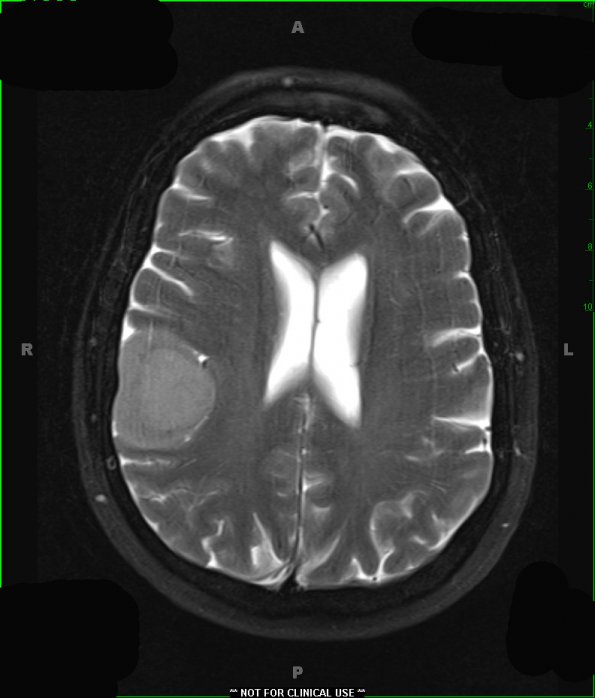

The T2 image with contrast is slightly hyperintense compared to the adjacent cortex.